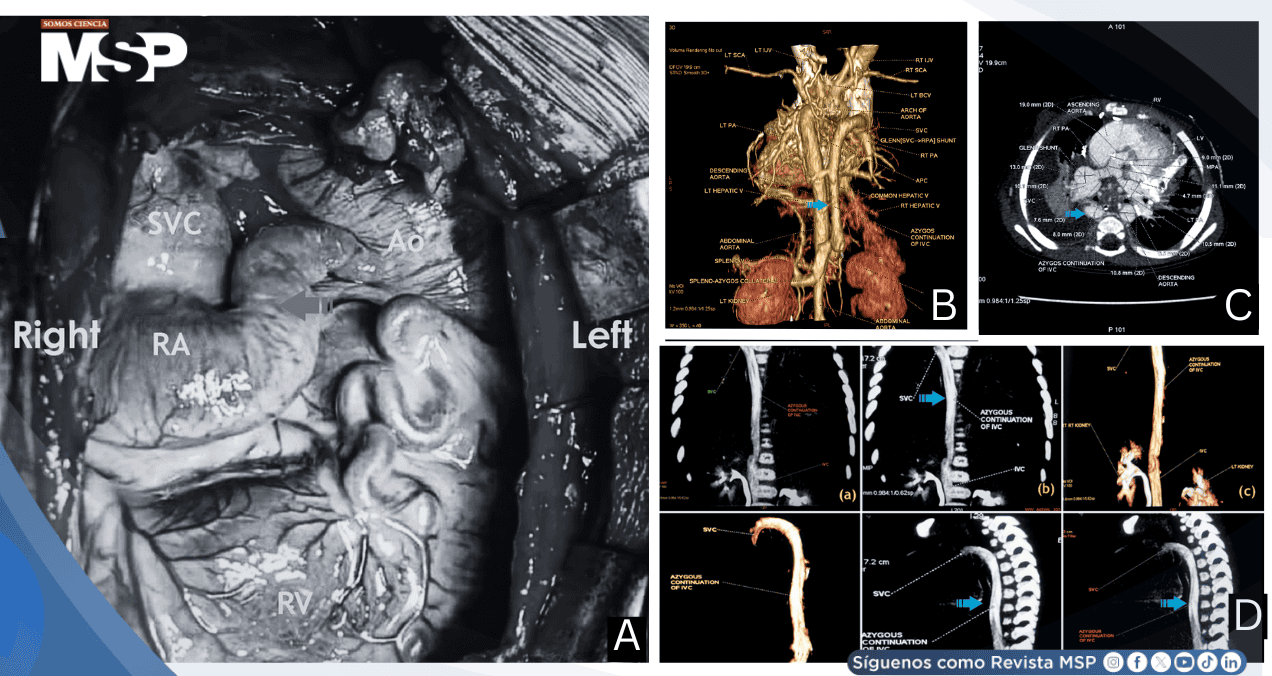

La segunda paciente presentaba ventrículo derecho de doble salida y ventrículo izquierdo de doble entrada, sin heterotaxia. La tomografía computarizada reveló arterias pulmonares de menor calibre con disparidad marcada: la arteria pulmonar derecha medía 7.1-7.2 mm, mientras que la izquierda mostraba estenosis proximal severa (2.6 mm proximalmente hasta 9.5 mm distalmente). La relación de McGoon fue 1.566 e índice de Nakata 396.12 mm²/m², valores significativamente menores que el primer caso.

El cateterismo preoperatorio ya mostraba hallazgos preocupantes: estrechamiento focal del 50% en la arteria pulmonar izquierda y flujo venoso retrógrado desde la vena cava superior hacia la inferior con retorno posterior, sugiriendo canales colaterales venosos preexistentes.

La cirugía fue más compleja, requiriendo 130 minutos de bypass. Además de la anastomosis cavopulmonar y ligadura del conducto, fue necesaria plastía de la arteria pulmonar izquierda. La presión de arteria pulmonar fue más elevada: 21/15 mmHg (media 17 mmHg).